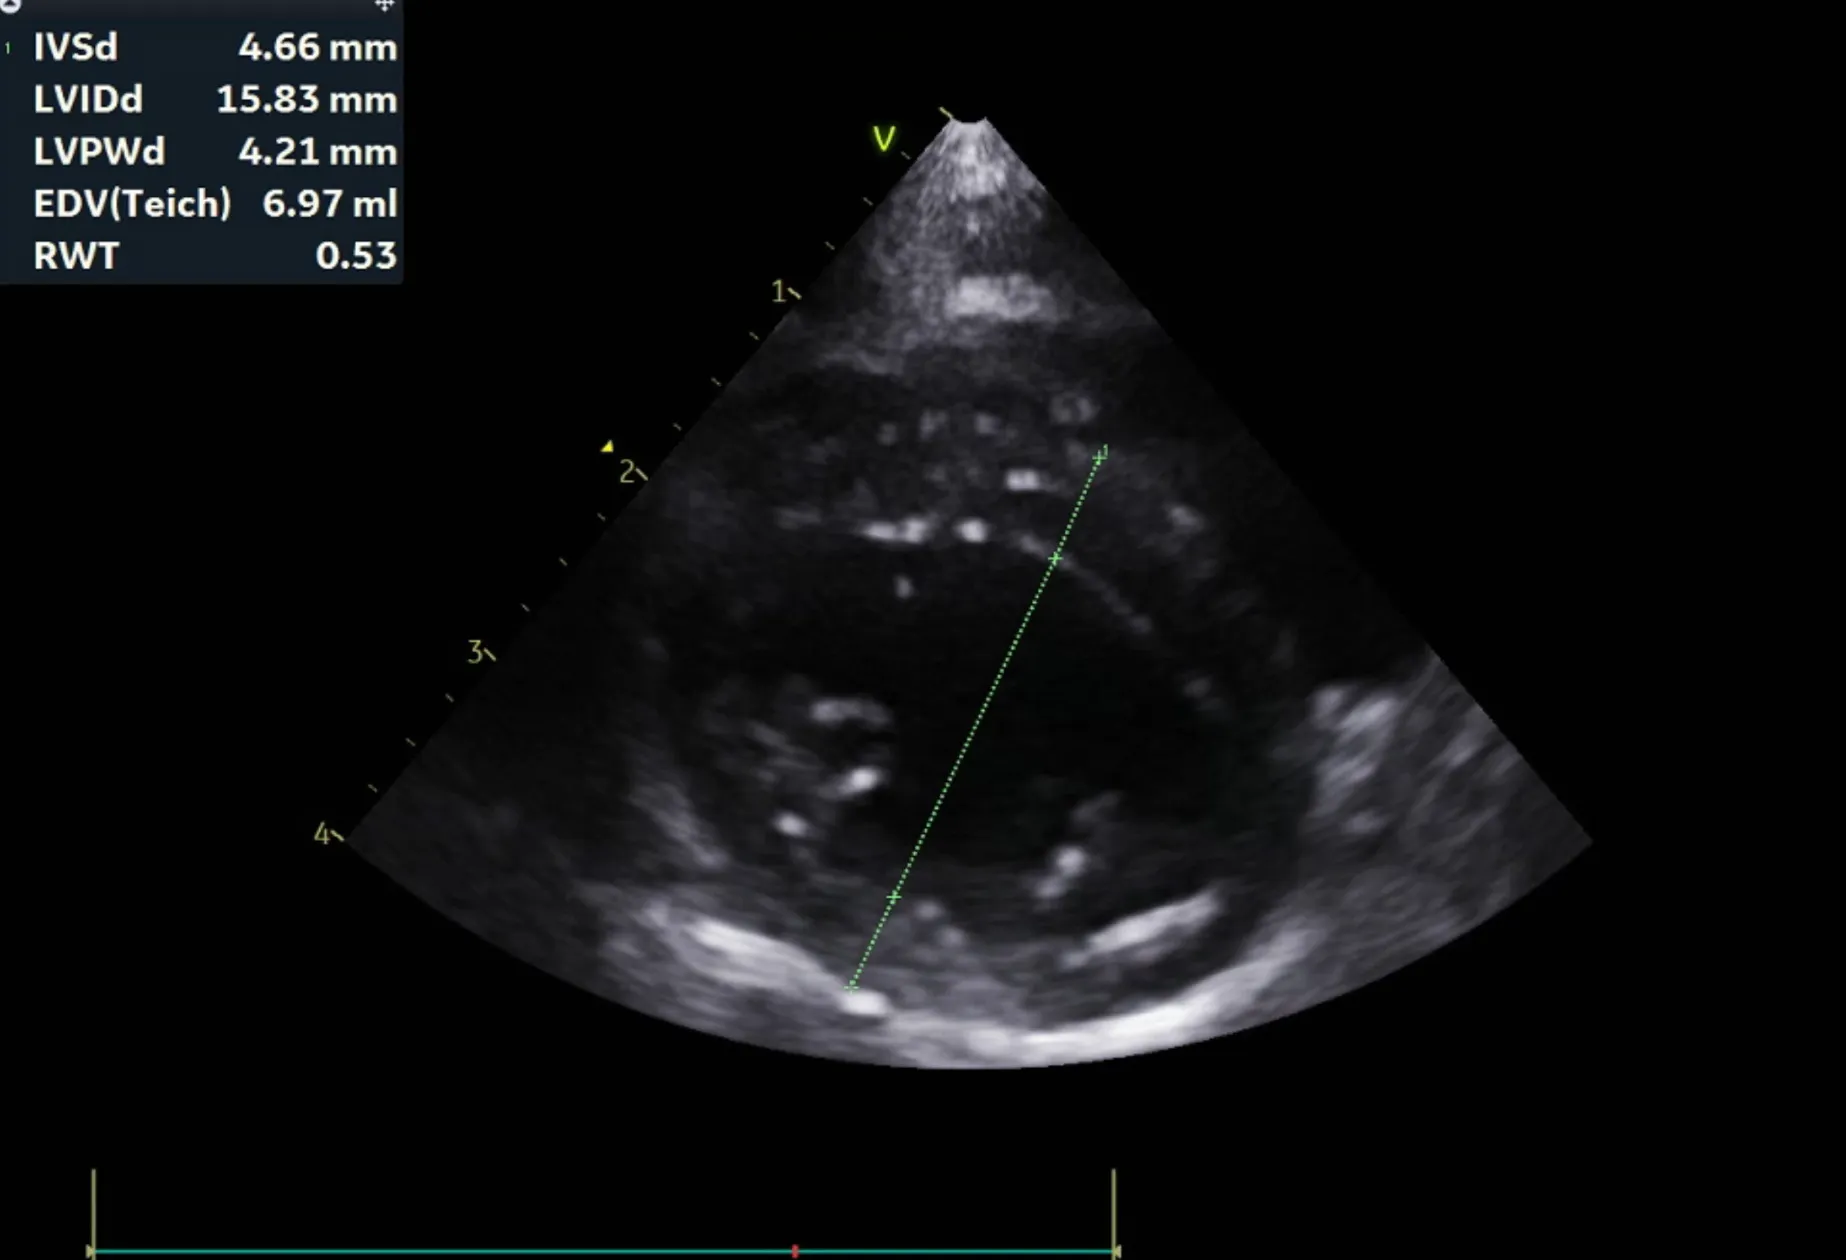

분류 수치

IVSd 4.66/4.58(2.80 - 4.90㎜) - 정상/정상

LVIDd 15.83/15.17(12.20 - 19.20㎜) - 정상/정상

LVPWd 4.21/4.09(2.80 - 4.80㎜) - 정상/정상

IVSs 6.06/5.17(4.30 - 8.40㎜) - 정상/정상

LVIDs 11.20/10.69(5.50 - 12.60㎜) - 정상/정상

LVPWs 4.66/5.02(4.60 - 8.50㎜) - 정상/정상

EF 59.9%/60.5%(40% - 67%) - 정상/정상

FS 29.3%/29.5%(30% - 49%) - 감소/감소

LVIDDN 0.98

EDVI 23(~100)

ESVI 9(~30)

Echo_comments

HCM으로 의심될만한 소견 관찰되지 않음

주치의 소견은 다음과 같습니다.

곰이 는 심장 초음파 검사 결과 현재 심잠벽의 두께는 정상이며 수축기능, 이완기능(심장이 정상적으로 잘 뛰는 것을 확인하는 검사) 모두 정상입니다.

심장 초음파는 1년에 한번씩 검사 받는 것을 추천드립니다.